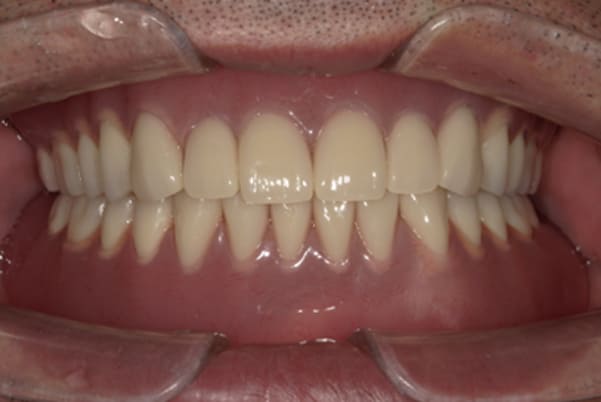

治療用入れ歯

-

精密義歯

治療用入れ歯は患者様とご相談し、早急にお痛みをとり、お食事ができることをご希望されていたため、歯を抜くと同時に仮の入れ歯が入りお食事をされた後のお写真です。直ちに、お痛みを取り除き、お食事ができるような治療計画としました。

精密義歯は、歯をぬいたあと歯肉が治ってから、精密な入れ歯を作製しました。治療中も、仮の入れ歯があるため、普段の生活に支障がなく、また仮の入れ歯を実際使ってのご意見、ご希望(バネが気になる)をお聞きした上で、精密な義歯に、ご希望を反映し作製しました。

従来の方法では、歯を抜いてから入れ歯を作るまでは、歯茎の治りを待つため数か月かかりますが、患者様のご希望で、見た目、食べることに支障が出ないよう、抜歯と同時に入れ歯を装着し、歯がない期間がない入れ歯を作製したため、その日から、お食事や外出が可能となりました。

また、当然ではありますが、患者様も残りの歯をこれ以上失いたくないとのご希望が強く可能な限り、残りの歯に負担がかからない機能性を重視し、また、バネがなるべく見えない設計とし、機能と審美の両方に重きをおいた入れ歯を作製し、お痛みなく、お食事も召し上がられるようになりました。